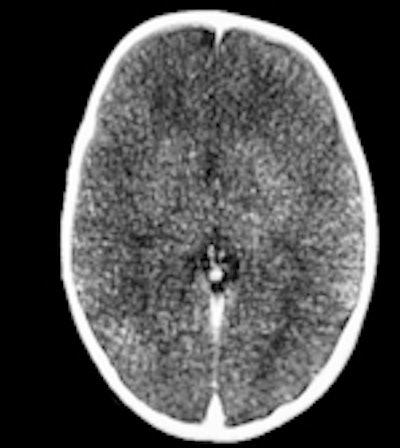

Ci-dessus: cet enfant a été retrouvé mort dans son lit; un scanner et un IRM post mortem ont été effectués un jour après l'heure du décès.

A gauche: scanner conventionnel, épaisseur de coupe de 5mm. A cause de la décomposition, il peut être difficile de différencier la matière grise et la substance blanche, même un jour après l'heure du décès. Au milieu: image 3D, rendu volumique. Cette technique permet dans certains cas de mieux maîtriser les changements post mortem dans l'atténuation cérébrale, mais il reste difficile de différencier les divers tissus cérébraux. Aucune pathologie n'a pu être détectée. A droite: l'IRM (séquence T2) offre une meilleure différentiation entre les divers tissus cérébraux. Si le corps a une température d'à peu près 10° C, les images IRM peuvent être assez bruyantes. Après le scanner et l'IRM, le syndrome de l'enfant battu a été exclu.Répondant aux questions des radiologues français, elle a expliqué que la technique pouvait être appliquée à des cadavres en état avancé de décomposition, du fait de la résistance surprenante des artères à la putréfaction. Son groupe a ainsi appliqué avec succès cette technique sur des cadavres au préalable gelés.